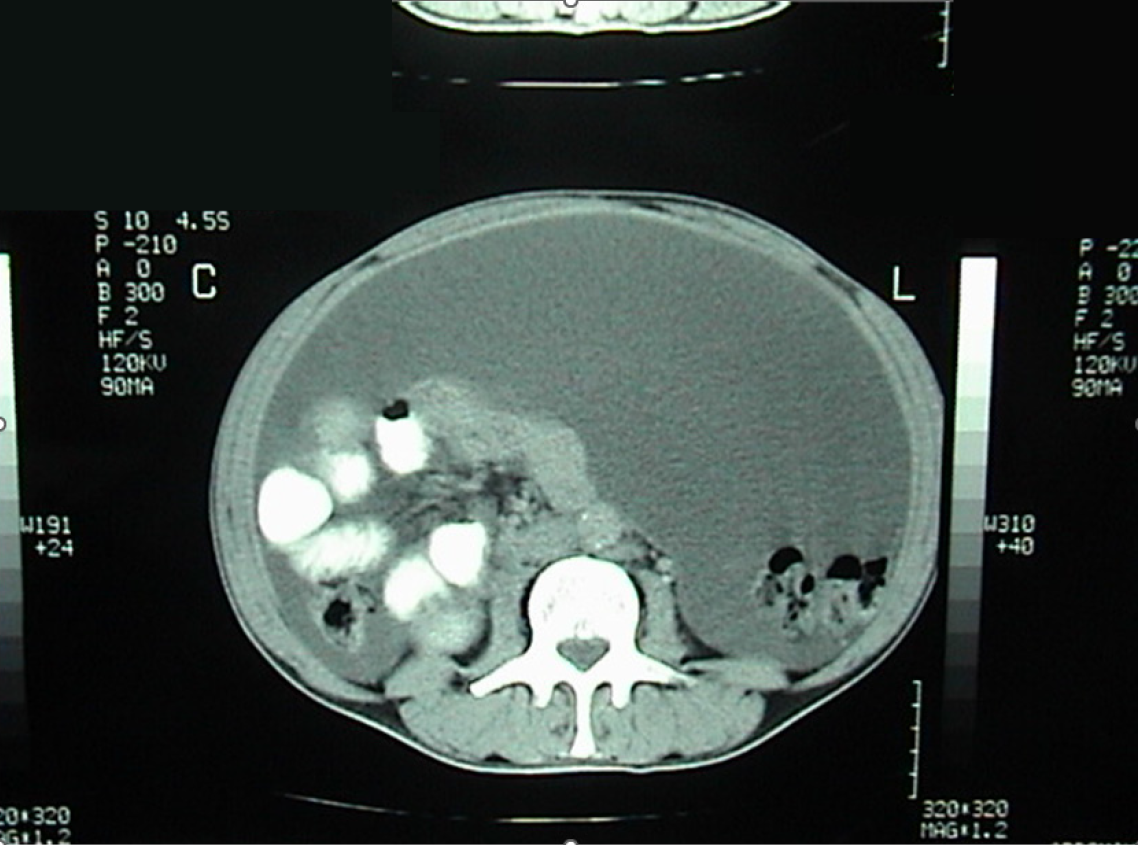

Figure 1 Enhanced computed tomography scan of the abdomen and pelvis showing a large amount of ascites.